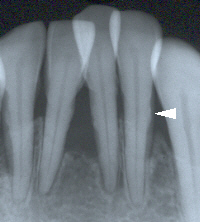

隣接面に付着している歯肉縁下歯石は

レントゲン写真で確認できることがある。